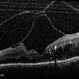

- vitreoschitic membrane

- vitreoschisis, myopic traction maculopathy

- Triamcinolone enhanced visualization of vitreoschisis membrane and removal in a case of myopic traction maculopathy.